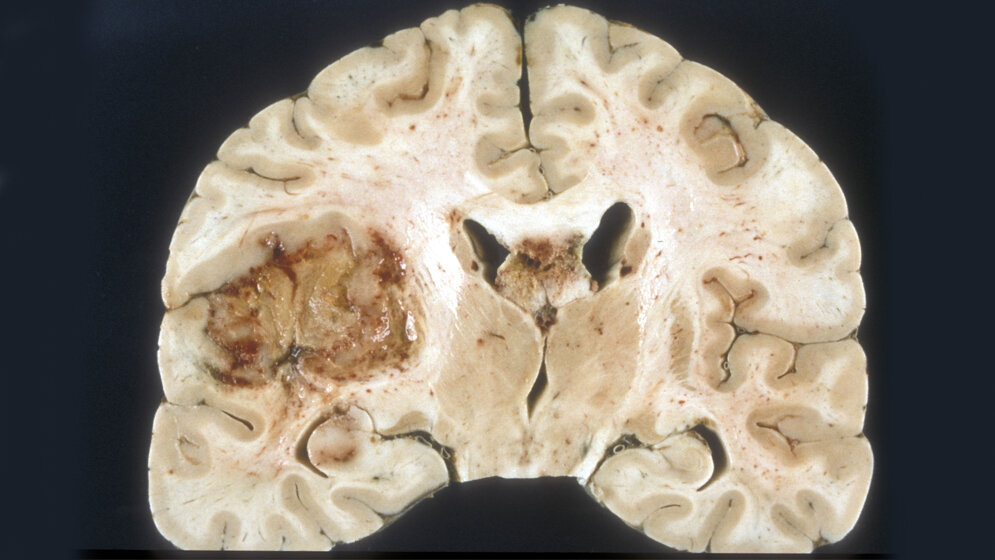

Hinter dem innovativen Ansatz steckt eine Methode, die beispielsweise bei Hauttumoren zum Einsatz kommt: die photodynamische Therapie. Zunächst werden hierfür die bösartigen Tumorzellen mithilfe einer chemischen Substanz (Photosensibilisator) selektiv lichtempfindlich gemacht und dann mit Licht geeigneter Wellenlänge bestrahlt, bis sie im Idealfall absterben (phototoxischer Effekt). Das in Ulm entwickelte, von einem Mikroprozessor gesteuerte LED-Implantat soll direkt im Gehirn an der Stelle platziert werden, an der durch die operative Entfernung des Glioblastoms die so genannte Resektionshöhle entstanden ist. Da Glioblastome meist innerhalb eines Saums von zwei Zentimetern um die Resektionshöhle herum erneut auftreten, sollen insbesondere die in diesem Bereich vorhandenen Tumorzellen durch die wiederholte Bestrahlung erreicht und zerstört werden. Die Eindringtiefe der verwendeten Strahlung in das Gewebe ist dabei Gegenstand aktueller Untersuchungen.

Das Implantat selbst besteht aus einem Glaskörper, in welchen LED integriert sind. Die LED sind in der Lage, Licht mit den Wellenlängen 405 und 635 nm sowie UV-Licht zu emittieren. Je größer die Wellenlänge, desto tiefer kann das Licht in Hirngewebe eindringen. Der Glaskörper kann den Dimensionen der durch die Entfernung des Glioblastoms entstandenen Resektionshöhle angepasst werden.